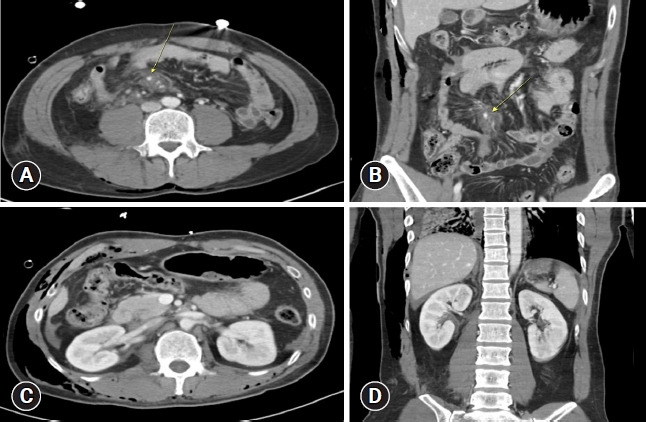

Traumatic ureteral injuries account for fewer than 1% of traumatic urologic injuries, and those caused by blunt trauma are even rarer than those caused by penetrating trauma. The symptoms associated with ureteral injury may be subtle, with or without hematuria, making it difficult to diagnose. We report the case of a 31-year-old man with a delayed diagnosis of proximal ureter injury after abdominal blunt trauma sustained in a motorcycle traffic accident. The patient underwent emergency laparotomy on admission for liver injury, mesenteric injury, and resultant hemoperitoneum. On postoperative day 6, he underwent angioembolization for suspected remnant intra-abdominal bleeding. Persistent symptoms of flank pain and leukocytosis led to follow-up imaging studies that revealed proximal ureter injury, and the patient underwent unilateral nephrectomy. This case stresses the importance of clinical suspicion for genitourinary injuries in the presence of abdominal trauma.

输尿管外伤在泌尿系统外伤中所占比例不到 1%,钝器外伤造成的输尿管外伤比穿透性外伤造成的输尿管外伤更为罕见。输尿管损伤的相关症状可能很隐蔽,伴有或不伴有血尿,因此很难诊断。我们报告了一例因摩托车交通事故造成腹部钝性外伤而导致输尿管近端损伤诊断延迟的 31 岁男性病例。患者入院时因肝脏损伤、肠系膜损伤和腹腔积血接受了急诊开腹手术。术后第 6 天,他因怀疑腹腔内残余出血而接受了血管栓塞术。持续的侧腹疼痛和白细胞增多症状导致后续影像学检查发现输尿管近端损伤,患者接受了单侧肾切除术。本病例强调了临床怀疑腹部创伤时泌尿生殖系统损伤的重要性。